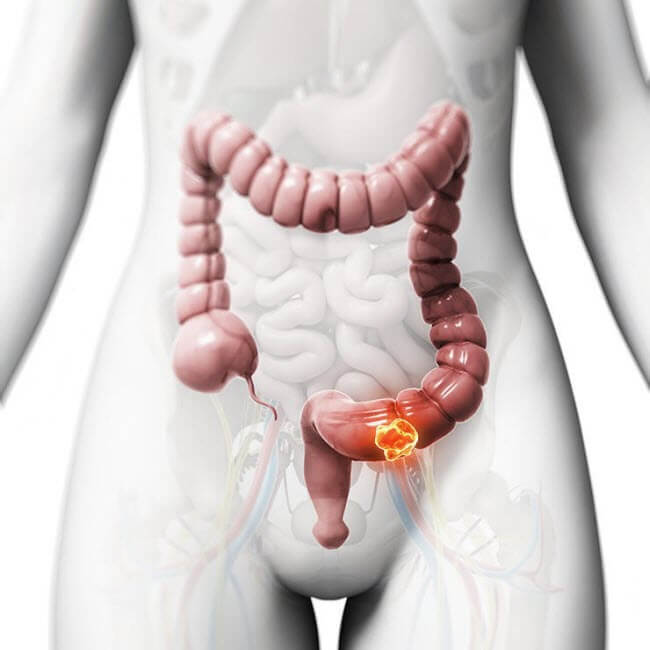

Рак кишечника вражає пряму кишку або товсту кишку і сфінктер, розвивається роками, після чого починає поширюватися і іншими частинами тіла.

У рік реєструють понад 41 тисячу випадків захворюваності, при цьому, дев’ять з десяти хворих старші за 50-ти років, однак, з кожним роком все більше людей страждають від цієї хвороби все в більш ранньому віці.

На ранніх стадіях він виліковний, але має один з найвищих показників смертності через несвоєчасну діагностику.